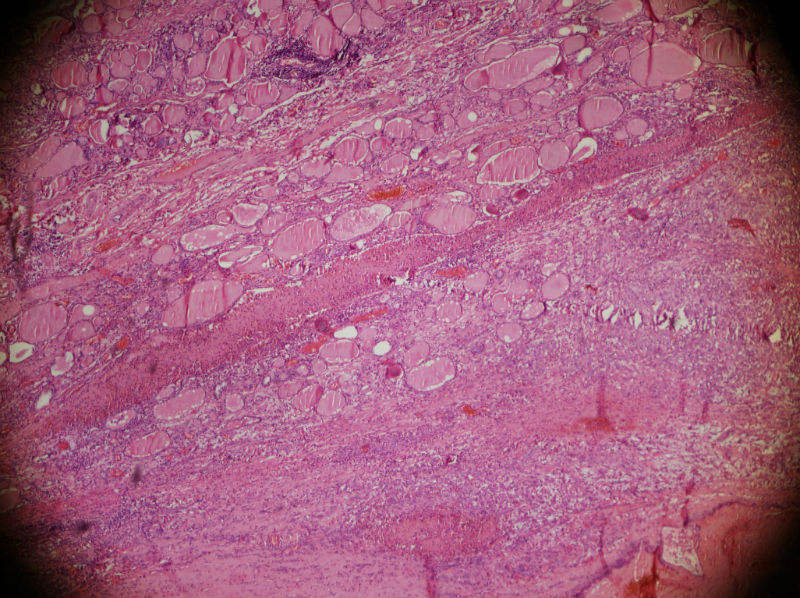

男,44,甲状腺囊肿.直径1.5公分,内流清亮液

• 甲状腺囊肿,请老师们指教图1

图1

结节性甲状腺肿伴出血、囊性变。囊肿边上的滤泡大小不一,纤维组织增生,还可见炎细胞浸润。